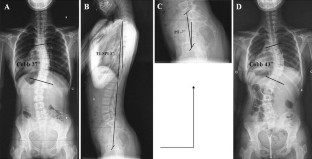

Fig. 1